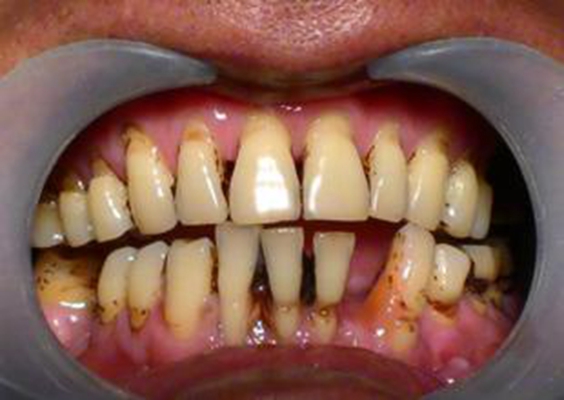

牙周炎圖片

牙周袋 (8)